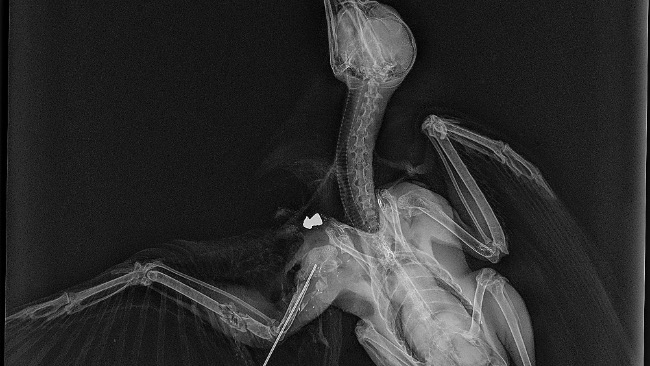

Ptak jest po zabiegu. Wybudził się bez powikłań. RTG pokazało, że jest OFIARĄ CZŁOWIEKA …Ktoś go POSTRZELIŁ !!! Brak słów…

Dodaje zdjęcia z prześwietleń, karty zabiegowej i paragonu z kliniki.